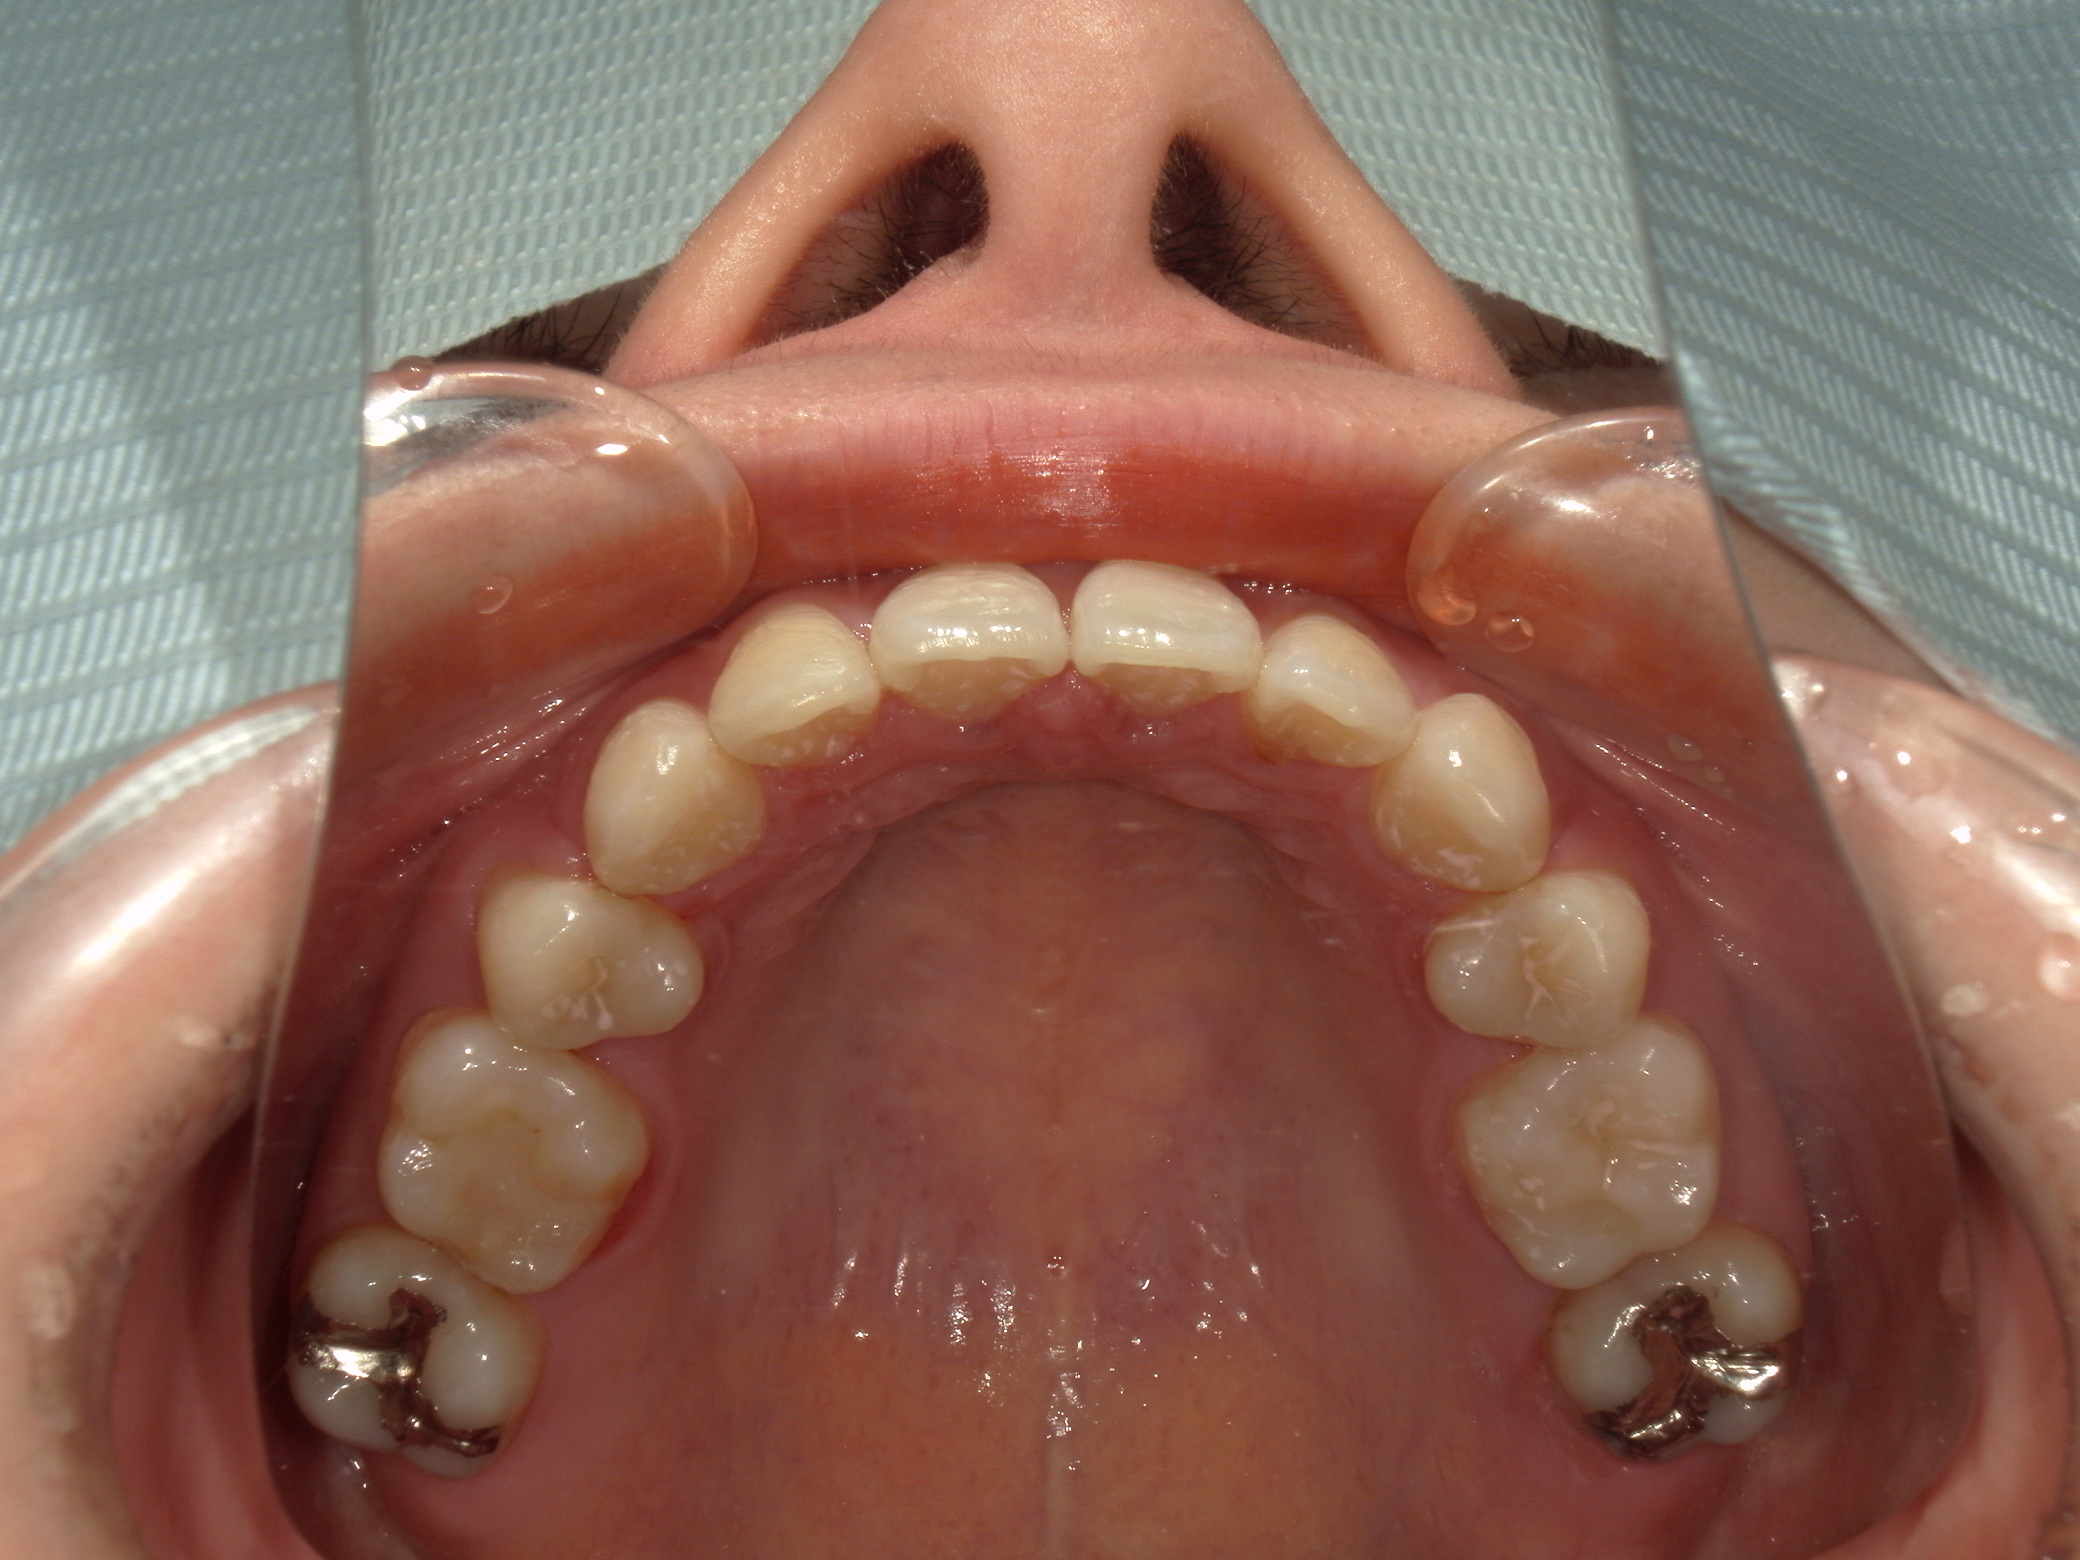

口元の突出を主訴に来院。

上下小臼歯抜歯により突出感を改善する計画を立てた。確立した咬合を崩さないように治療を進める事を目標とした。

患者はハーフリンガル矯正を希望した。

治療後、口元の突出感の改善、咬合関係は維持することができた。